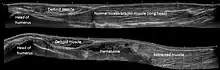

Musculoskeletal

Musculoskeletal ultrasound is used to examine tendons, muscles, nerves, ligaments, soft tissue masses, and bone surfaces.[40] It is helpful in diagnosing ligament sprains, muscles strains and joint pathology. It is an alternative or supplement to x-ray imaging in detecting fractures of the wrist, elbow and shoulder for patients up to 12 years[41] (Fracture sonography).

Quantitative ultrasound is an adjunct musculoskeletal test for myopathic disease in children;[42][43] estimates of lean body mass in adults;[44] proxy measures of muscle quality (i.e., tissue composition)[45] in older adults with sarcopenia[46][47]